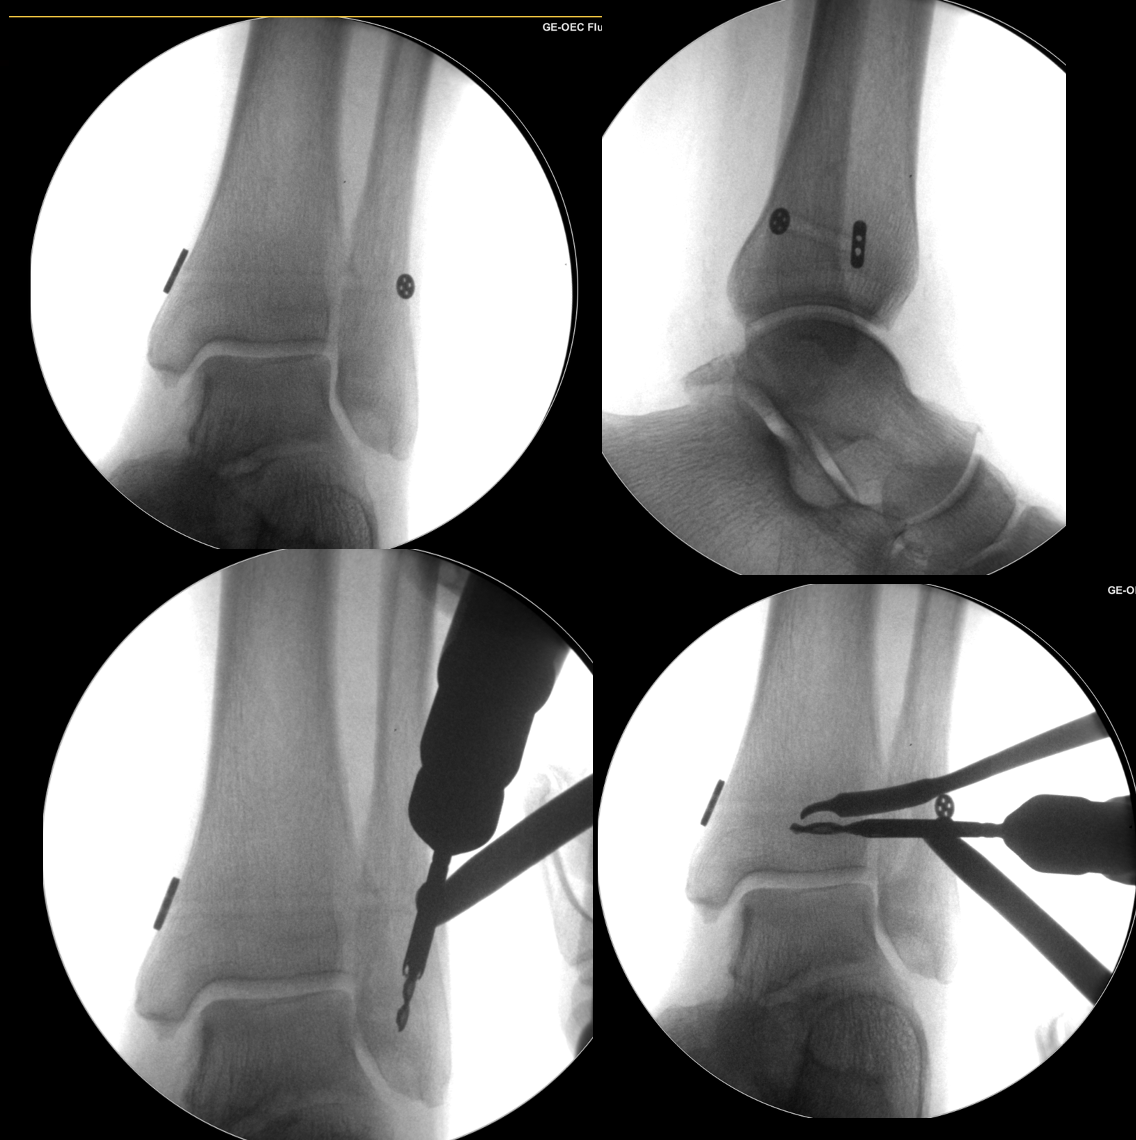

syndesmosis reconstruction surgery

Fig 3. Intraoperative fluoroscopic images demonstrating a tightrope device reconstruction (top row) and then supplementation with the AITFL internal brace procedure (bottom row)